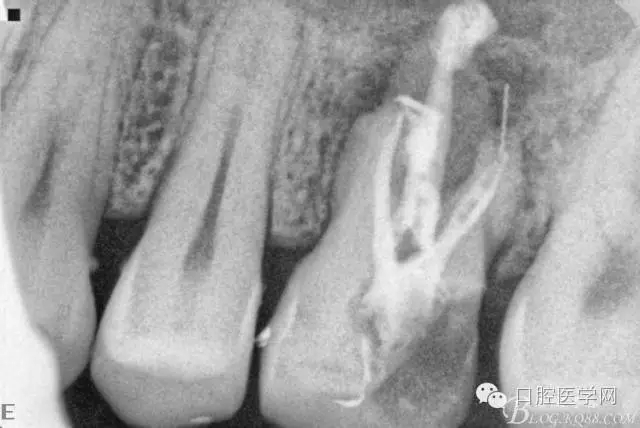

擴根片(可惜遠頰根有一斷針)